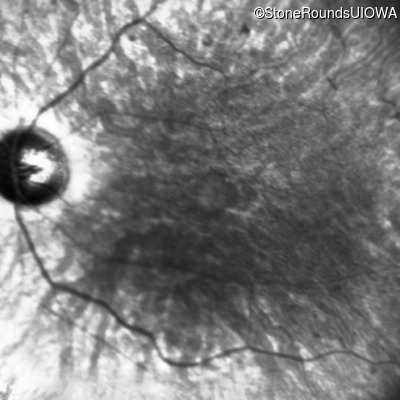

This 21 year old man first had difficulty seeing the blackboard in the 5th grade. Two years later he began having difficulty seeing in dim light. In high school he was approximately 50 pounds overweight, but was able to lose that weight with a strict diet.

| Bardet Biedl Syndrome | BBS1 | Met390Arg ATG>AGG | Arg277Lys AG(G)>AA(G) | AR |